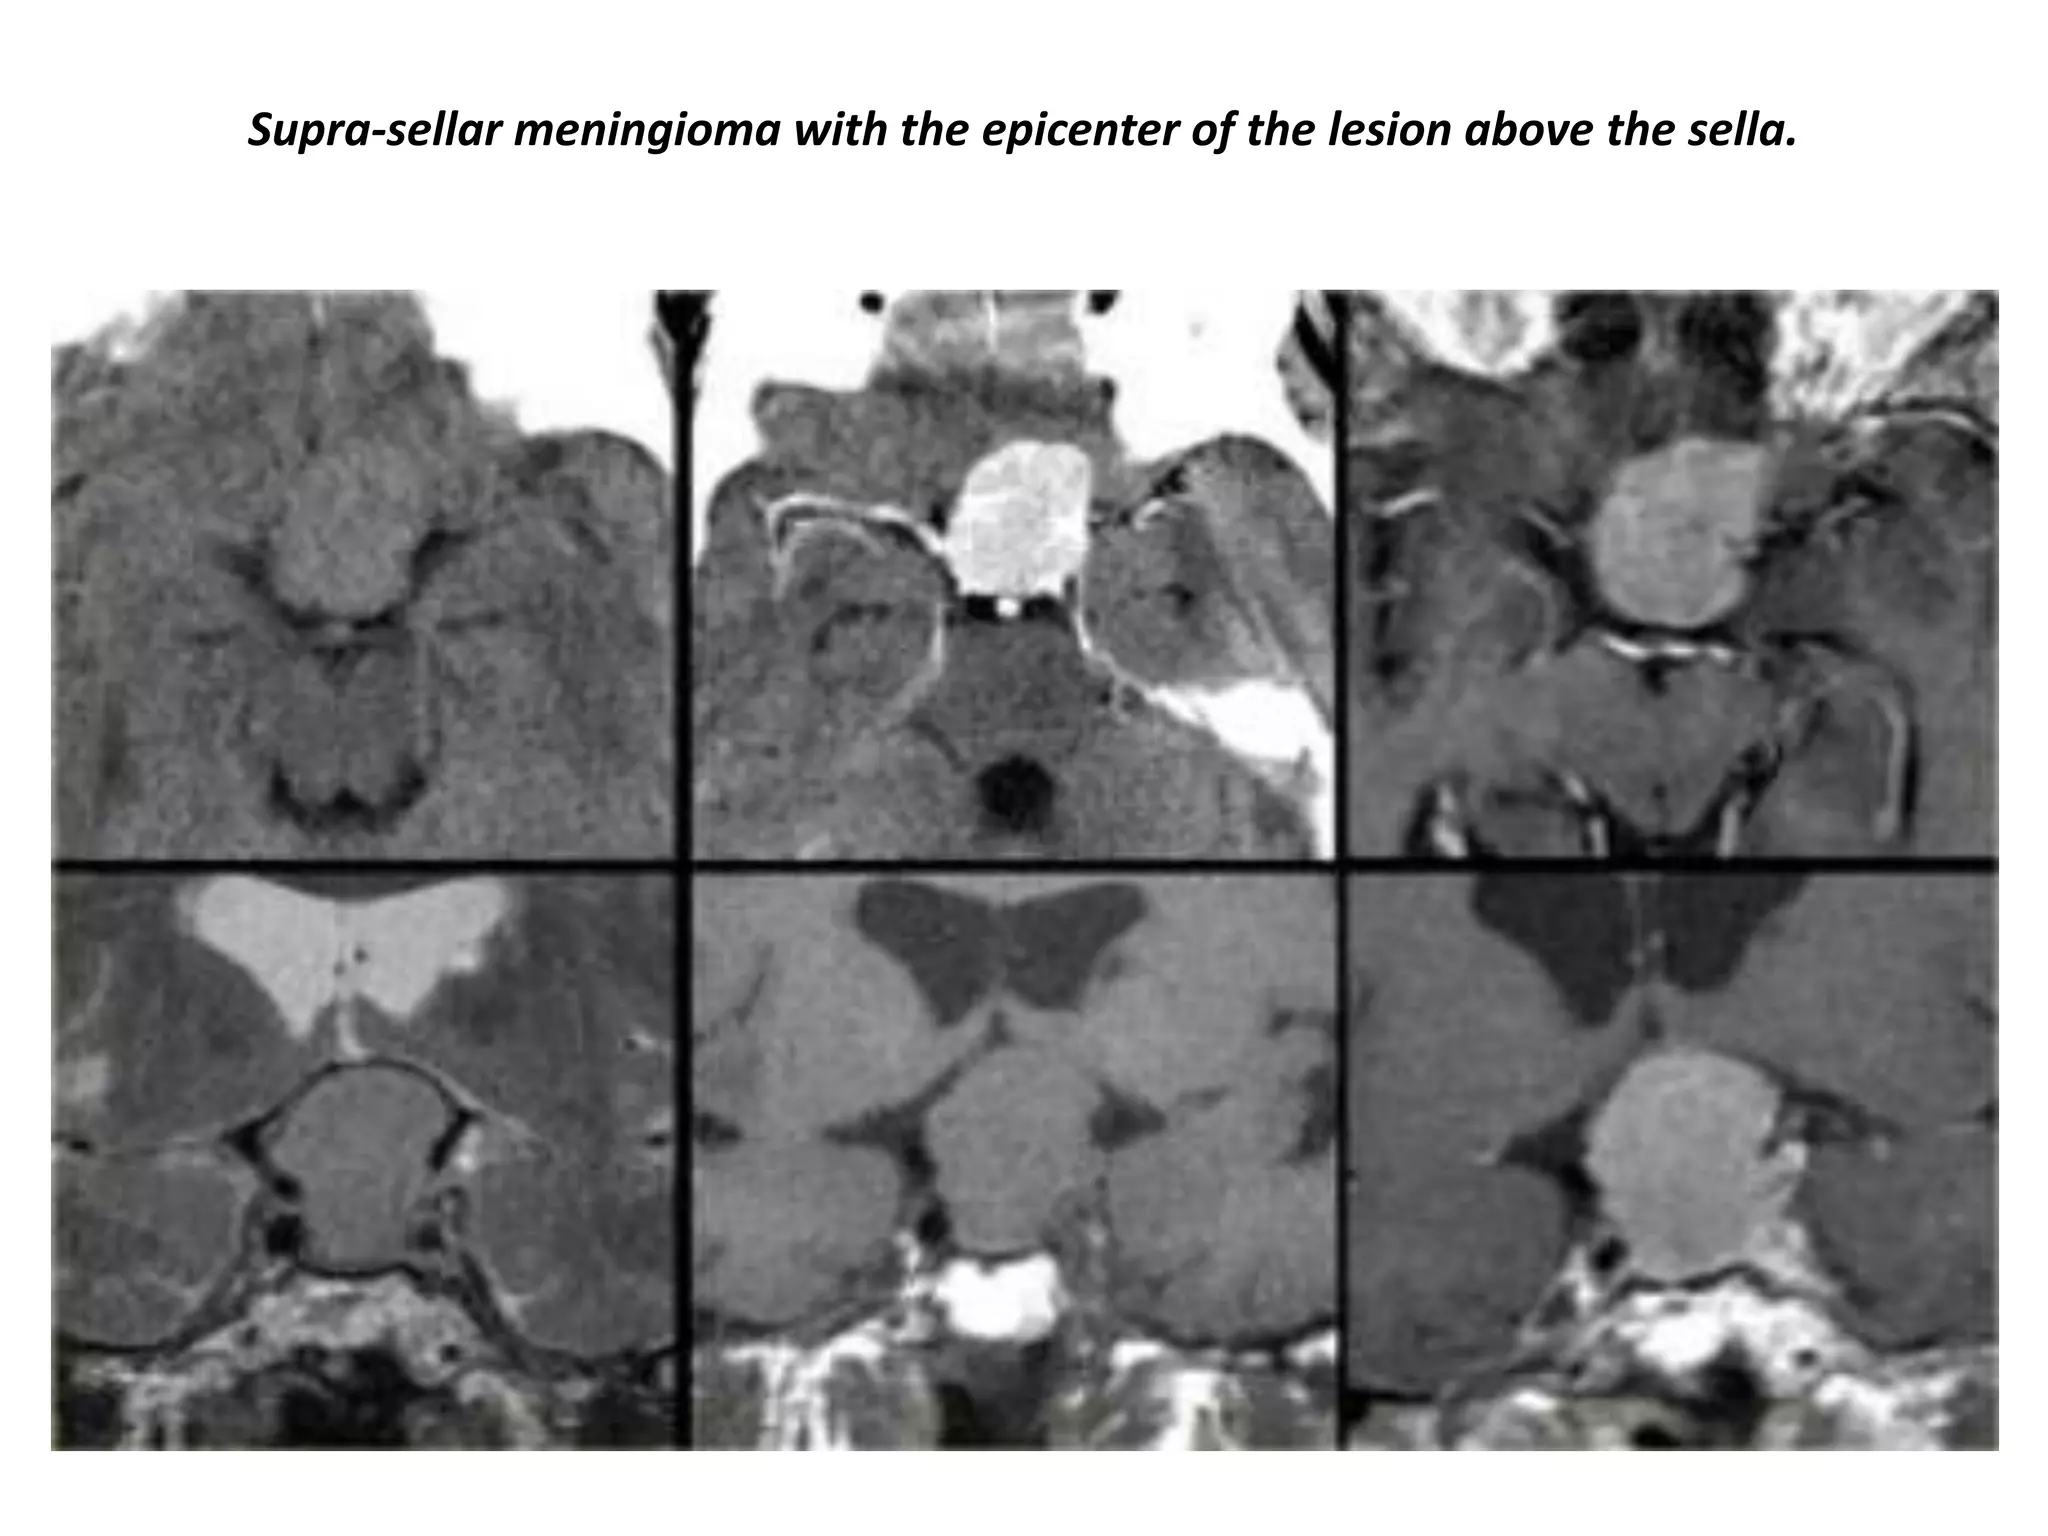

Supra-sellar meningioma with the epicenter of the lesion above the sella.

Sagittal images of the same case (Suprasellar meningioma) with the epicenter of the

lesion above the sella.

Supra-sellar meningioma with intra-sellar extension.